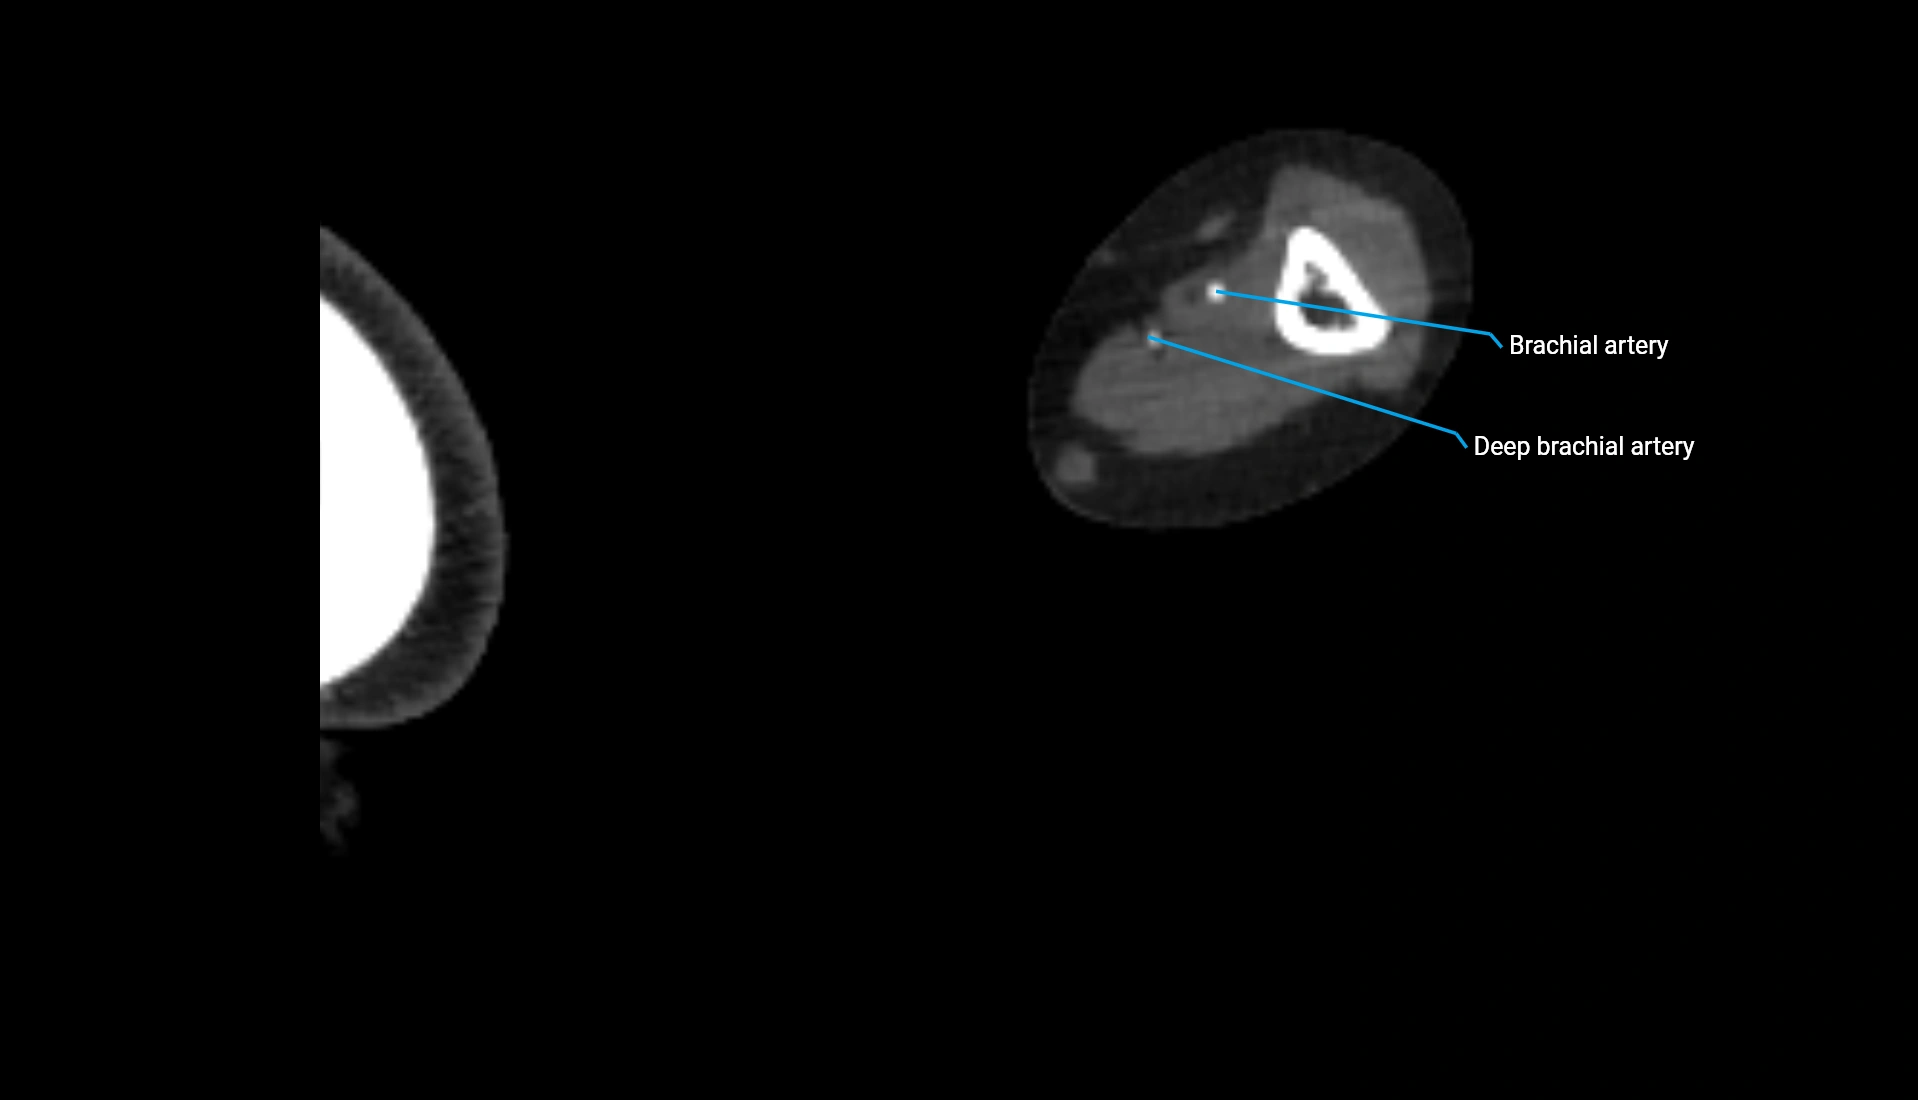

CT Appearance

Non-Contrast CT:

• Cortex: High-density, sharply defined

• Subchondral bone: Dense cancellous matrix

• Articular surface: Smooth concave contour articulating with the capitellum

• Excellent for evaluating bone integrity, alignment, and subtle fractures

Post-Contrast CT:

• Bone: No enhancement

• Joint capsule and synovium: Mild enhancement outlining the joint

• Improves contrast between soft tissues and bony margins

• Useful in detecting subtle joint abnormalities or postoperative changes